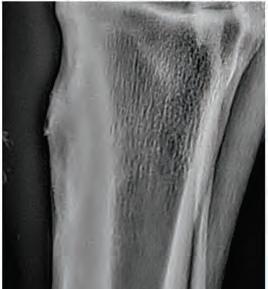

Bilateral hind cannon radiographs of X XXXX XXXXXX were taken on 14th April 21 and again 17th May 21 and 14th June 21. Initial radiographs showed a 32mm longitudinal non displaced left mid cannon saucer fracture extending 6mm into the dorsal cortex and a 44mm longitudinal displaced fracture right mid cannon 5.5mm in depth mid dorsal cortex associated proximally with a 27mm x 6.5mm secondary fracture (see right). Initially, surgical removal was recommended of the R H fracture fragment. A second series was taken on 17th May and third series on 14th June see right. Both fractures have attached and integrated with the parent bone with minor surface enthesophyte formation and periosteal activity evident.